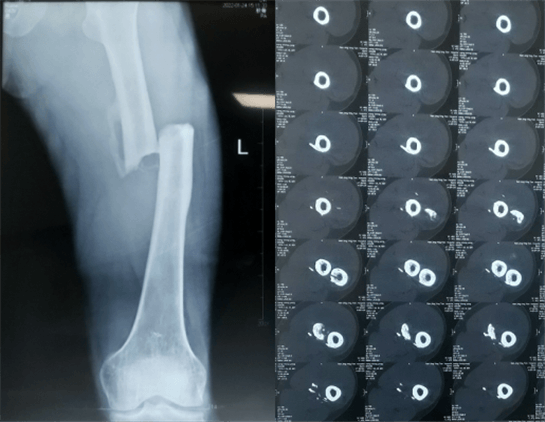

患者:男性,43歲,左股骨干骨折髓內釘內固定術

醫(yī)院:南京應天骨科醫(yī)院

股骨是下肢的主要負重骨,有其特殊的解剖關系,周圍肌肉發(fā)達,因此一旦股骨干骨折后如果治療不當,容易造成肌肉牽拉,導致畸形和功能障礙。治療股骨干骨折,必須遵循恢復肢體的長度及力線,無旋轉,盡量行以微創(chuàng),保護骨折局部血運,促進愈合。髓內釘對骨折的固定能夠達到較大的穩(wěn)定性和堅固性,可以減少醫(yī)源性污染,減少軟組織分離及周圍血供破壞,有利于骨折早期愈合,是治療股骨干骨折的首要治療方法。

術前檢查